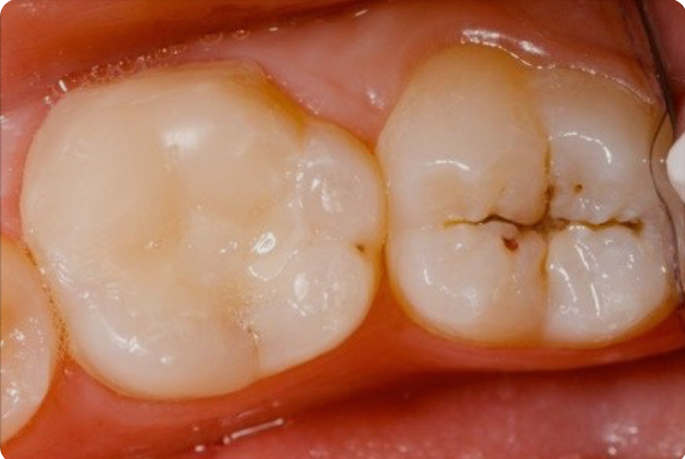

- Las caries iniciales no duelen. En etapas tempranas, una caries puede tratarse con procedimientos mínimos. Si se deja avanzar, puede requerir tratamientos más complejos como endodoncia o incluso extracción.

Fig. 1. Caries incipiente